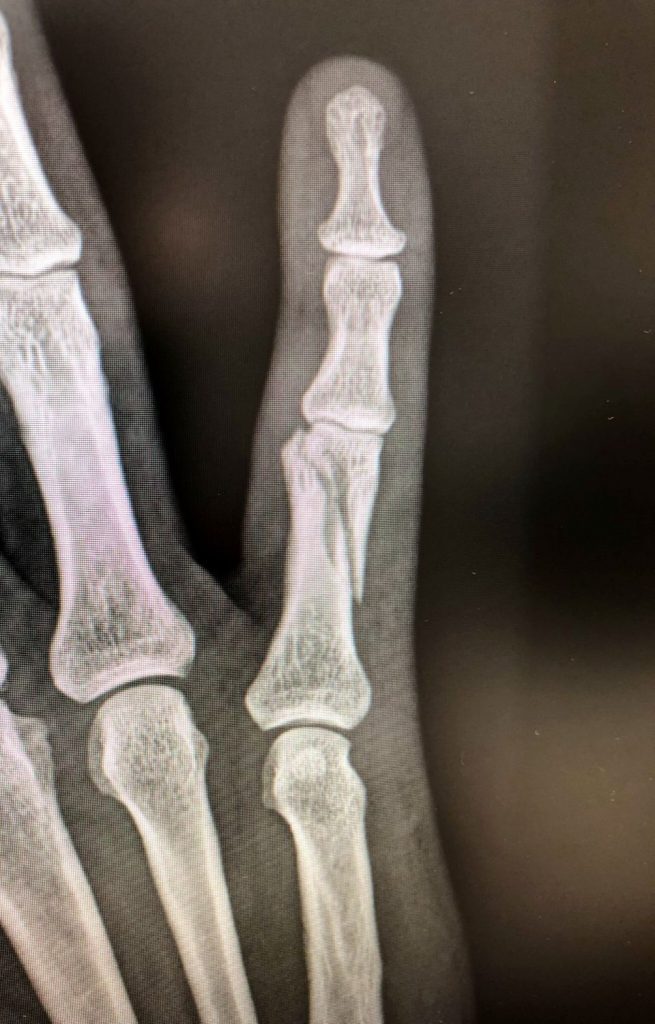

Figura 3 - Fractura conminuta falange proximal 3º dedo. (Ver también Figura 7).

Algunas fracturas se producen en la diáfisis (el tronco) del hueso, mientras que otras afectan a la articulación (intra-articulares). Las fracturas conminutas (cuando el hueso se fractura en múltiples fragmentos) por lo general se producen por traumatismos de alta energía y suelen ser inestables.

Figura 7 - Osteosíntesis con placa y tornillos de falange proximal 3º dedo.